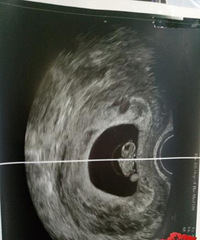

八年不孕,中药不知道喝了多少,试管一次成功

一位妈妈的试管成功案例,分享给需要的集美。文章来自萝卜兔子宝贝。 八年不孕,试管一次成功,分享我的双胎路~和老公结婚八年未孕,中药不知道喝了多少,各种检查记不得做了多少次,身体上的痛苦可以忍受但心理的伤痛难以形容 虽然老公和公婆都不说什么,但我知道他们很想要孩子